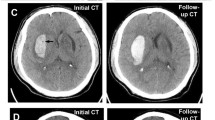

Two trained vascular neurologists (CHY and KYS) who were anonymized to the clinical information and prognosis independently reviewed NCCT scans after the initial training session of 100 patients external to our analysis. Qualitative NCCT markers of HE (heterogeneous density, black hole sign, blend sign, irregular shape, island sign, and satellite sign) were identified with a visual inspection (Fig. 1). Hematomas with heterogenous density and irregular shape were investigated on the axial NCCT slice that showed the largest hematoma area, according to the shape and density scales suggested by Barras et al. [3, 9] The density and shape scales are two separate 5-point categorical scales, and each scales range from category 1 (regular in shape scale and homogenous in density scale) to category 5 (irregular in shape scale and heterogenous in density scale). Heterogenous density and irregular shape was defined as shape and density scale of category 3, 4, or 5. Hematomas with heterogenous density and irregular shape were defined as shape and density scale of III, IV, or V on the axial NCCT slice showing the largest hematoma area as Barras et al. suggested [3, 9]. Black hole sign was defined as relatively hypoattenuated lesion, with a density difference at least 28 Hounsfield units (HU) compared with surrounding hematoma [20]. The definition of blend sign was coexistence of well demarcated hypodensity lesion and hyperdensity lesion with density difference of more than 18 HU [10]. Island sign was referred to as the presence of ≥ 3 small hematomas completely separated or ≥ 4 small hematomas partly separated from the main hematoma [11]. Satellite sign was defined as small hematoma (≤ 10 mm) separated from the main hematoma, with distance of 1 to 20 mm on at least one slice of the NCCT scan [21]. Discrepancies between the two readers (17 heterogenous densities, 7 black hole signs, 19 blend signs, 31 irregular shapes, 35 island signs, and 27 satellite signs) were adjudicated by joint discussion until a consensus was reached.

Representative cases of small ICHs with or without NCCT markers. a ICH without any qualitative NCCT markers that expanded in follow-up CT scan after 2 h from the baseline scan. Baseline hematoma density (mean HU) was 51.7 HU. b ICH with heterogeneous densities (black arrows) that did not expand in follow-up CT scan after 21 h from the baseline scan. Baseline hematoma density (mean HU) was 55.0 HU. c ICH with satellite sign (black arrow), blend sign (dashed black arrow), and black hole sign (white arrow) that did not expand in follow-up CT scan after 23 h from the baseline scan. Baseline hematoma density (mean HU) was 58.4 HU. d ICH with irregular shape and island sign (black arrows) that did not expand in follow-up CT scan after 10 h from the baseline scan. Baseline hematoma density (mean HU) was 57.1 HU. CT, computed tomography, HU, Hounsfield unit, ICH, intracerebral hemorrhage, NCCT, noncontrast computed tomography